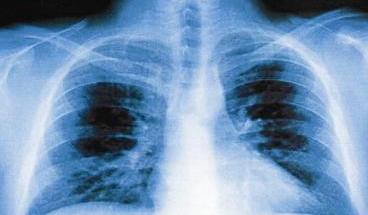

معظم وفيات وباء الأنفلونزا بسبب الالتهاب الرئوي

وعام 1918م التي سميت «سنة الرحمة» عرفت تلك السنة بسنة انتشار وباء الانفلونزا الذي اجتاح العالم وقيل انه قضى على ما بين 25 الى 50 مليون انسان. لم تنج الكويت منه فقد ذكر المعتمد السياسي الكولونيل ر. ا. هاملتون في تقريره لعام 1918م «ومع نهاية شهر اكتوبر تعرضت الكويت لوباء الانفلونزا الذي دخل كل بيت تقريبا وتضاعف الامر باصابة البعض بالالتهاب الرئوي.

قدرت الوفيات بأربعة آلاف شخص وظل المرض حتى شهر ديسمبر من العام نفسه». وسمَّى الكويتيون هذه السنة «بسنة الرحمة» حيث ظنوا بادئ الامر انها مقدمة لوباء الطاعون ولكن الله لطف بهم ورحمهم.

وعام 1918م التي سميت «سنة الرحمة» عرفت تلك السنة بسنة انتشار وباء الانفلونزا الذي اجتاح العالم وقيل انه قضى على ما بين 25 الى 50 مليون انسان. لم تنج الكويت منه فقد ذكر المعتمد السياسي الكولونيل ر. ا. هاملتون في تقريره لعام 1918م «ومع نهاية شهر اكتوبر تعرضت الكويت لوباء الانفلونزا الذي دخل كل بيت تقريبا وتضاعف الامر باصابة البعض بالالتهاب الرئوي.

قدرت الوفيات بأربعة آلاف شخص وظل المرض حتى شهر ديسمبر من العام نفسه». وسمَّى الكويتيون هذه السنة «بسنة الرحمة» حيث ظنوا بادئ الامر انها مقدمة لوباء الطاعون ولكن الله لطف بهم ورحمهم.